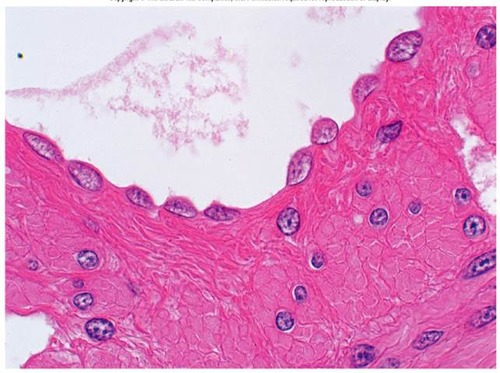

Stratified Squamous

- Named for cells present at the free (apical) surface, which are flattened

- Functions as a protective covering where friction is common

- Locations - lining of the:

* Skin (outer portion)

* Mouth

* Esophagus